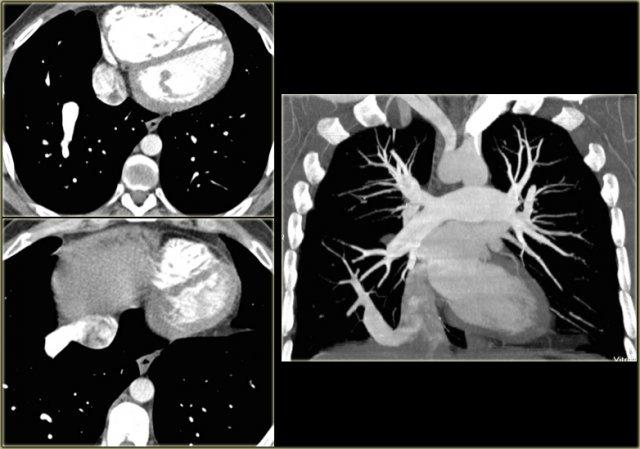

Double Aortic Arch

On the left a chest film of a 6-month old boy with stridor and cough.

The trachea is deviated to the left, otherwise the chest film is normal.

So there is some mass effect on the right side.

On the left the reconstructions demonstrating a double aortic arch.

There are branches coming off the right arch and branches coming off the left arch.

The right arch is typically larger and higher than the left.

There is a complete ring that encircles the esophagus and the trachea and usually there is stridor or dysphagia.

Two brachiocephalic arteries arise on each side separately (four vessel sign).

On the left a chest film of a young adult with a cough.

There is a right paratracheal mass.

The differential diagnosis is tumor, adenopathy or vessel (right arch, dilated azygos vein, dilated aberrant right subclavian artery).

On the left axial images and posterior view of volume rendered reconstruction.

Describe the findings and then continue.

The findings are:

- four vessel sign

- double arch

- right arch higher and larger

- esophagus and trachea are completely encircled

The narrowing of the trachea is seen on the axial images, but better appreciated on the MPR and Volume Rendered image.

On the left preoperative and postoperative MDCT studies of a 2-month-old female infant with double aortic arch presenting with stridor and repeated apnea.

The smaller left arch is partially resected.